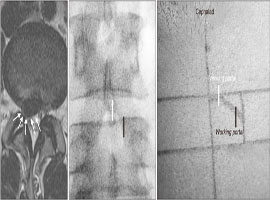

BESS 도 디스크를 목적으로 했던 Uniportal 에서 사용 범위가 확장되어 협착증에도 사용할 수 있는 Biportal 로 수술 가능하게 되었습니다.

| [전문] 허리가 옆으로 굽었어요! 청소년기 및 소아에서도 볼 수 있는 '척추측만증' Scoliosis (0) | 2020.12.11 |

| [전문] 척추가 앞으로 빠져나왔어요! Spondylolisthesis (0) | 2020.12.10 |